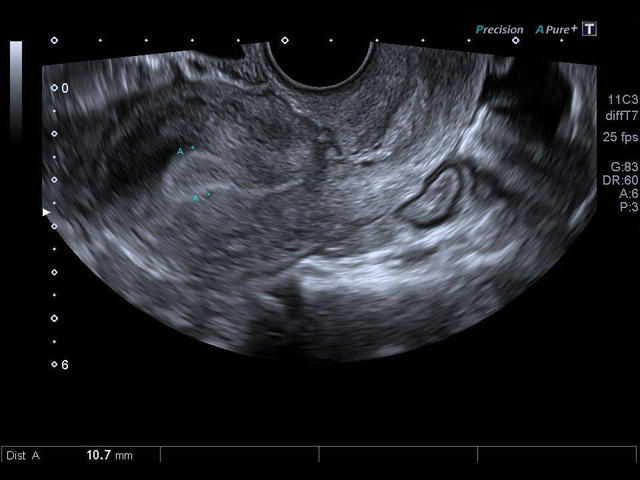

- Гинекология

- Полостной конвексный

- Полостной биплановый (конвексный+линейный)

- Высокотехнологичное сложное многолучевое сканирование с режимом подавления спекл-шумов в реальном времени - Aplipure plus.

- Одновременная обработка множества смежных ультразвуковых линий Precision Imaging